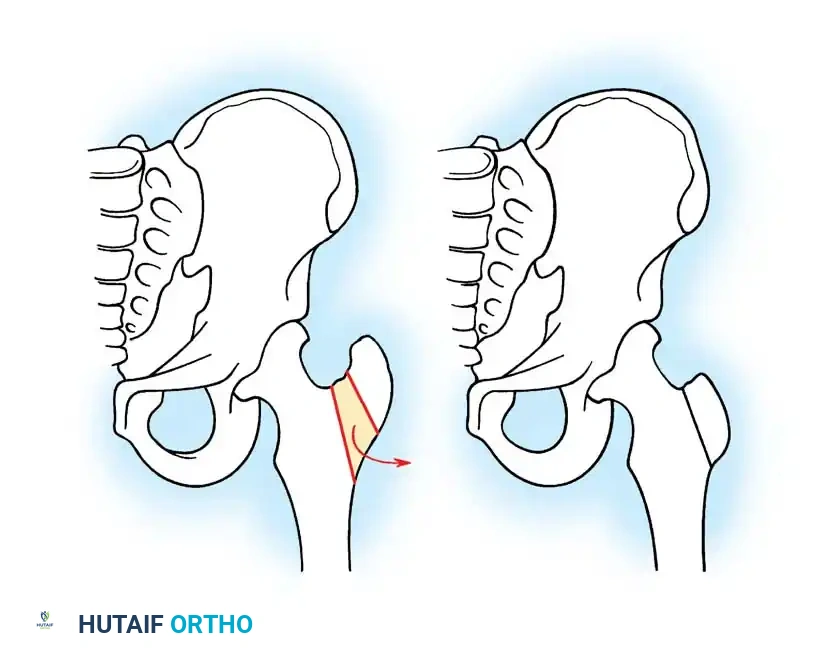

Salter Innominate Osteotomy Technique:

1. Approach: A Smith-Petersen (anterior) approach is utilized. The interval between the tensor fasciae latae and the sartorius is developed.

2. Exposure: The iliac apophysis is split, and the inner and outer tables of the ilium are stripped subperiosteally down to the greater sciatic notch.

3. Osteotomy: A Gigli saw is passed through the sciatic notch and directed anteriorly to exit at the anterior inferior iliac spine (AIIS).

4. Redirection: The distal acetabular fragment is hinged on the pubic symphysis and rotated anterolaterally, pivoting on the triradiate cartilage.

5. Grafting and Fixation: A triangular wedge of bone (harvested from the anterior iliac crest) is impacted into the osteotomy gap. The construct is stabilized with two or three threaded Kirschner wires driven from the proximal ilium, through the graft, and into the distal fragment.